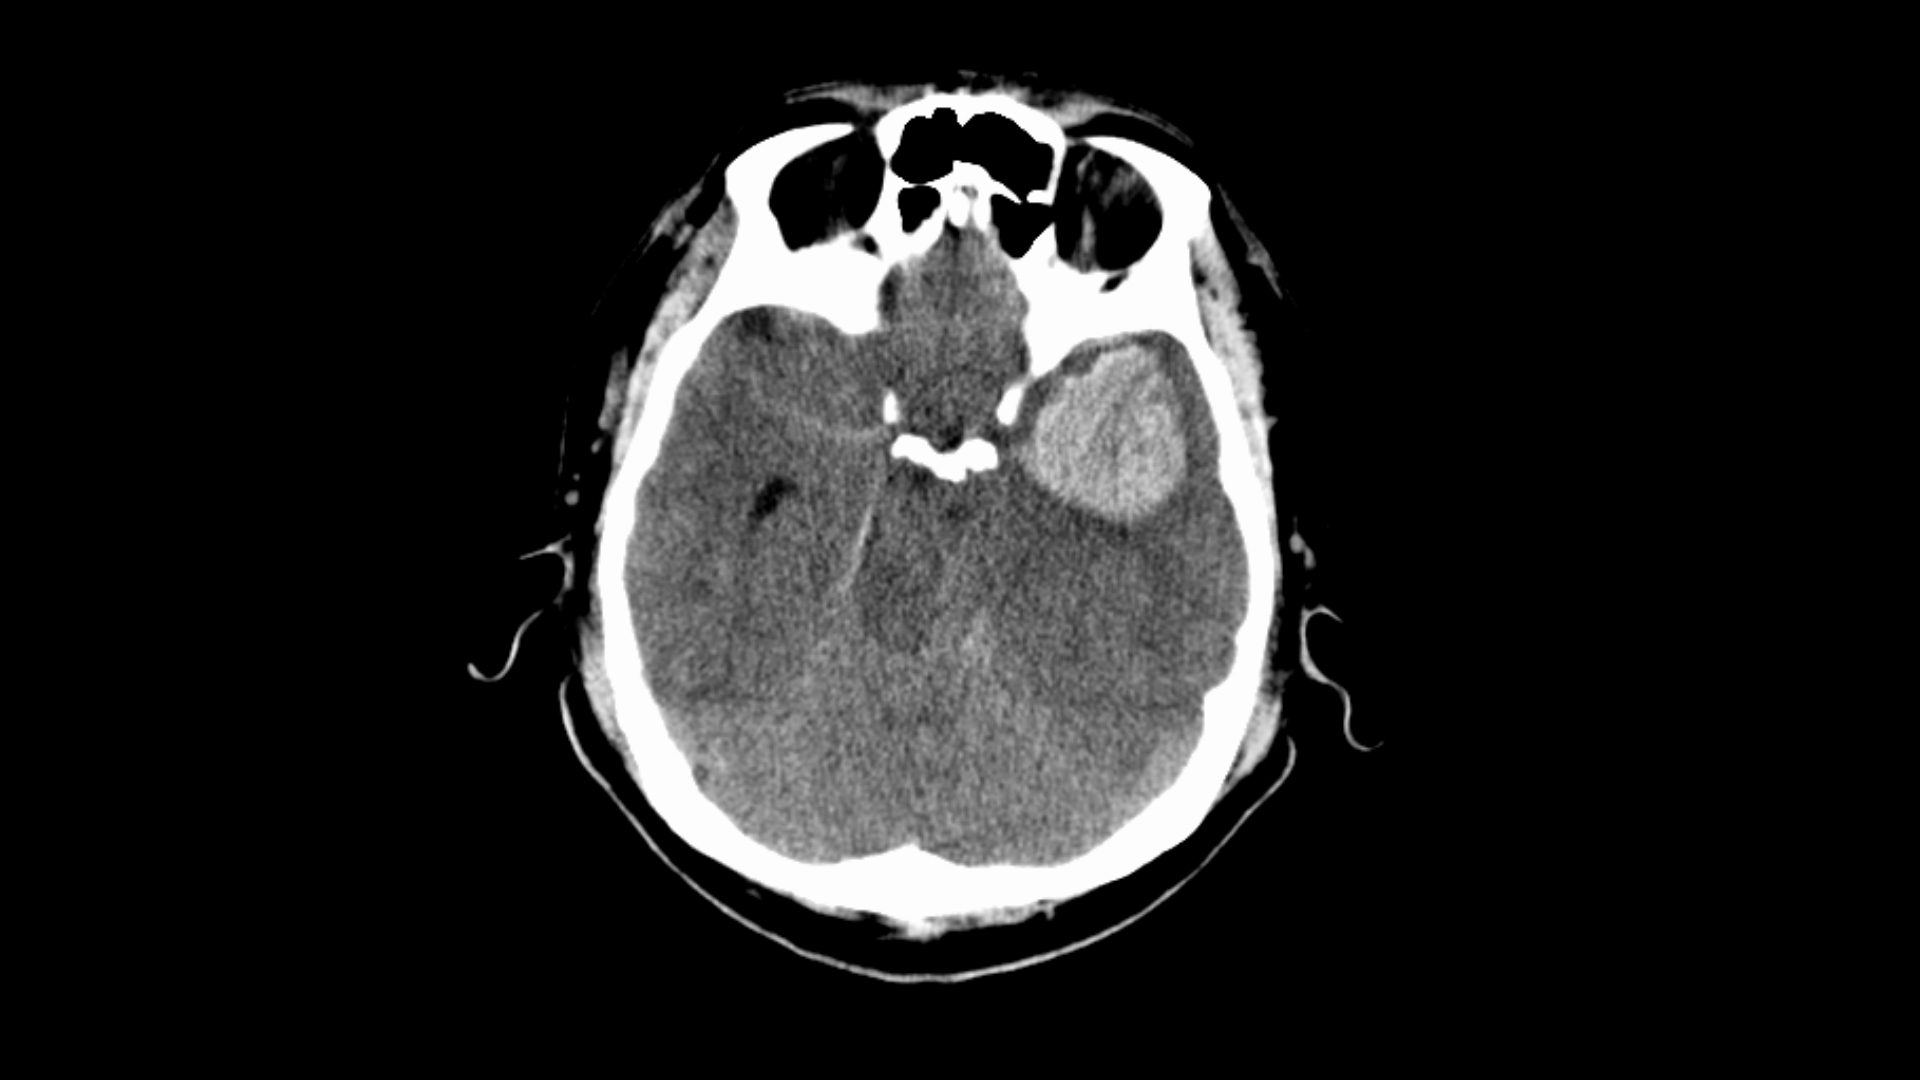

頭部外傷

痙攣で搬送された40歳代男性 実践 画像診断q A 羊土社 レジデントノート 羊土社